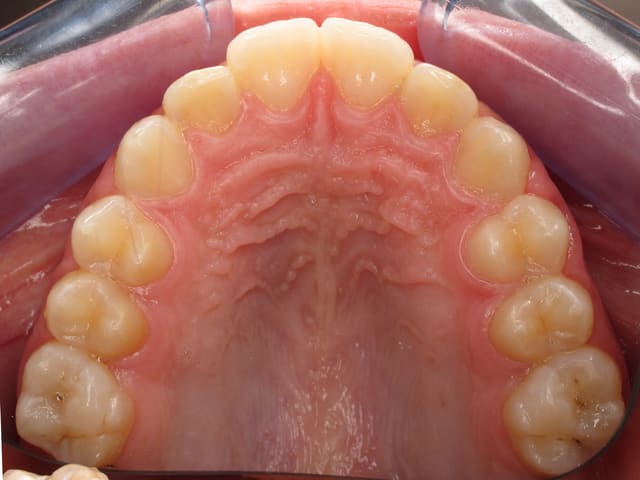

b)Vues occlusales

Le patient doit ouvrir aussi largement qu’il le peut sans effort. Le miroir occlusal doit être inséré à 45 degrés, le plus postérieurement possible. Il doit donner une image symétrique. Il ne doit pas y avoir contact avec les surfaces dentaires. Le cliché sera pris à 45 degrés par rapport au miroir, réalisant un cliché orienté à 90 degrés par rapport aux faces occlusales.

L’image doit inclure le secteur antérieur jusqu’à au moins la surface distale de la première molaire. Au mieux le cliché inclura toutes les dents. La face vestibulaire des dents ne doit pas être visible.

Le centre de l’image est formé par l’intersection du plan sagittal et d’une ligne joignant horizontalement les deuxièmes prémolaires. Le rapport de grandissement est d’environ 1 :2.

Au maxillaire, le miroir s’appuiera sur la muqueuse en distal des dernières molaires, et sur les incisives mandibulaires. Le centre de l’image est de la même façon l’intersection entre la ligne du plan sagittal et une ligne horizontale joignant les deuxièmes prémolaires. Au maxillaire, le praticien se place derrière le patient."